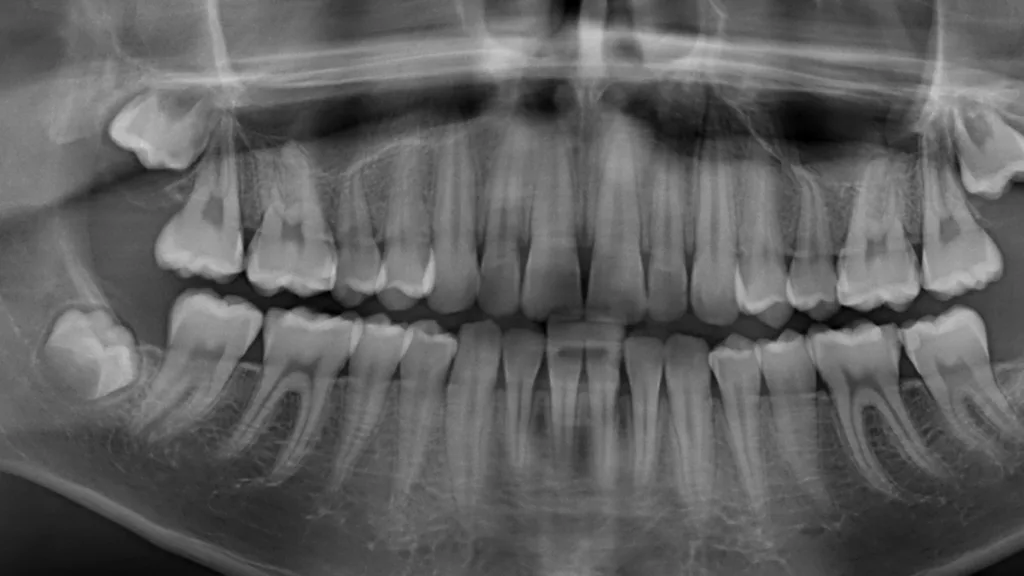

Die Ehlers-Danlos-Syndrome sind eine heterogene Gruppe von 13 unterschiedlichen Bindegewebserkrankungen, die alle durch Gelenkshypermobilitäten und überdehnbare und fragile Haut charakterisiert sind und je nach Typ mit unterschiedlichen weiteren Symptomen assoziiert sind [9]. Das parodontale Ehlers-Danlos-Syndrom (pEDS) ist das einzige der Ehlers-Danlos-Syndrome, das sich mit einer schweren Parodontitis im jugendlichen Alter, teilweise auch schon im Milchgebiss, manifestiert, da die Mutationen primär Gene der unspezifischen Immunantwort betreffen und erst in weiterer Folge die Bindegewebsschwäche verursachen [8] (Abb. 5, Abb. 6).

Die klinische Diagnose basiert auf der Trias der rasch progredienten Parodontitis im Teenageralter, dem kompletten Fehlen der befestigten Gingiva und der auffallenden Neigung zur Bildung von Hämatomen, die in zirka 80% der Betroffenen zu persistierenden Hämosiderin-Einlagerungen an den Schienbeinen führt. Die Parodontitis manifestiert sich teilweise schon im Milchgebiss, teilweise erst während der Pubertät und führt unbehandelt in wenigen Jahren zur Zahnlosigkeit. Das pEDS wird autosomal-dominant vererbt, sodass mindestens ein Elternteil ebenso an pEDS erkrankt ist; sehr selten kann es sich um eine Neumutation handeln. Die genetische Diagnose stützt sich auf die klinische Verdachtsdiagnose und wird durch den Nachweis pathogener Mutationen in den Komplement-1-Genen des C1S oder C1R gesichert.